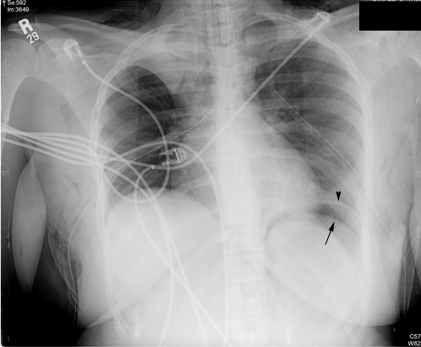

One day later, bilateral chest tubes have drained the pneumothoraces. RUL atelectasis persists and the pneumoperitoneum is more easily appreciated on the left. This case demonstrates that alveolar rupture can result in air tracking to the mediastinum, the subcutaneous tissues, the pleurae and (rarely) the peritoneum.

Arrowhead points to left diaphragm.

Arrow points to pneumoperitoneum.